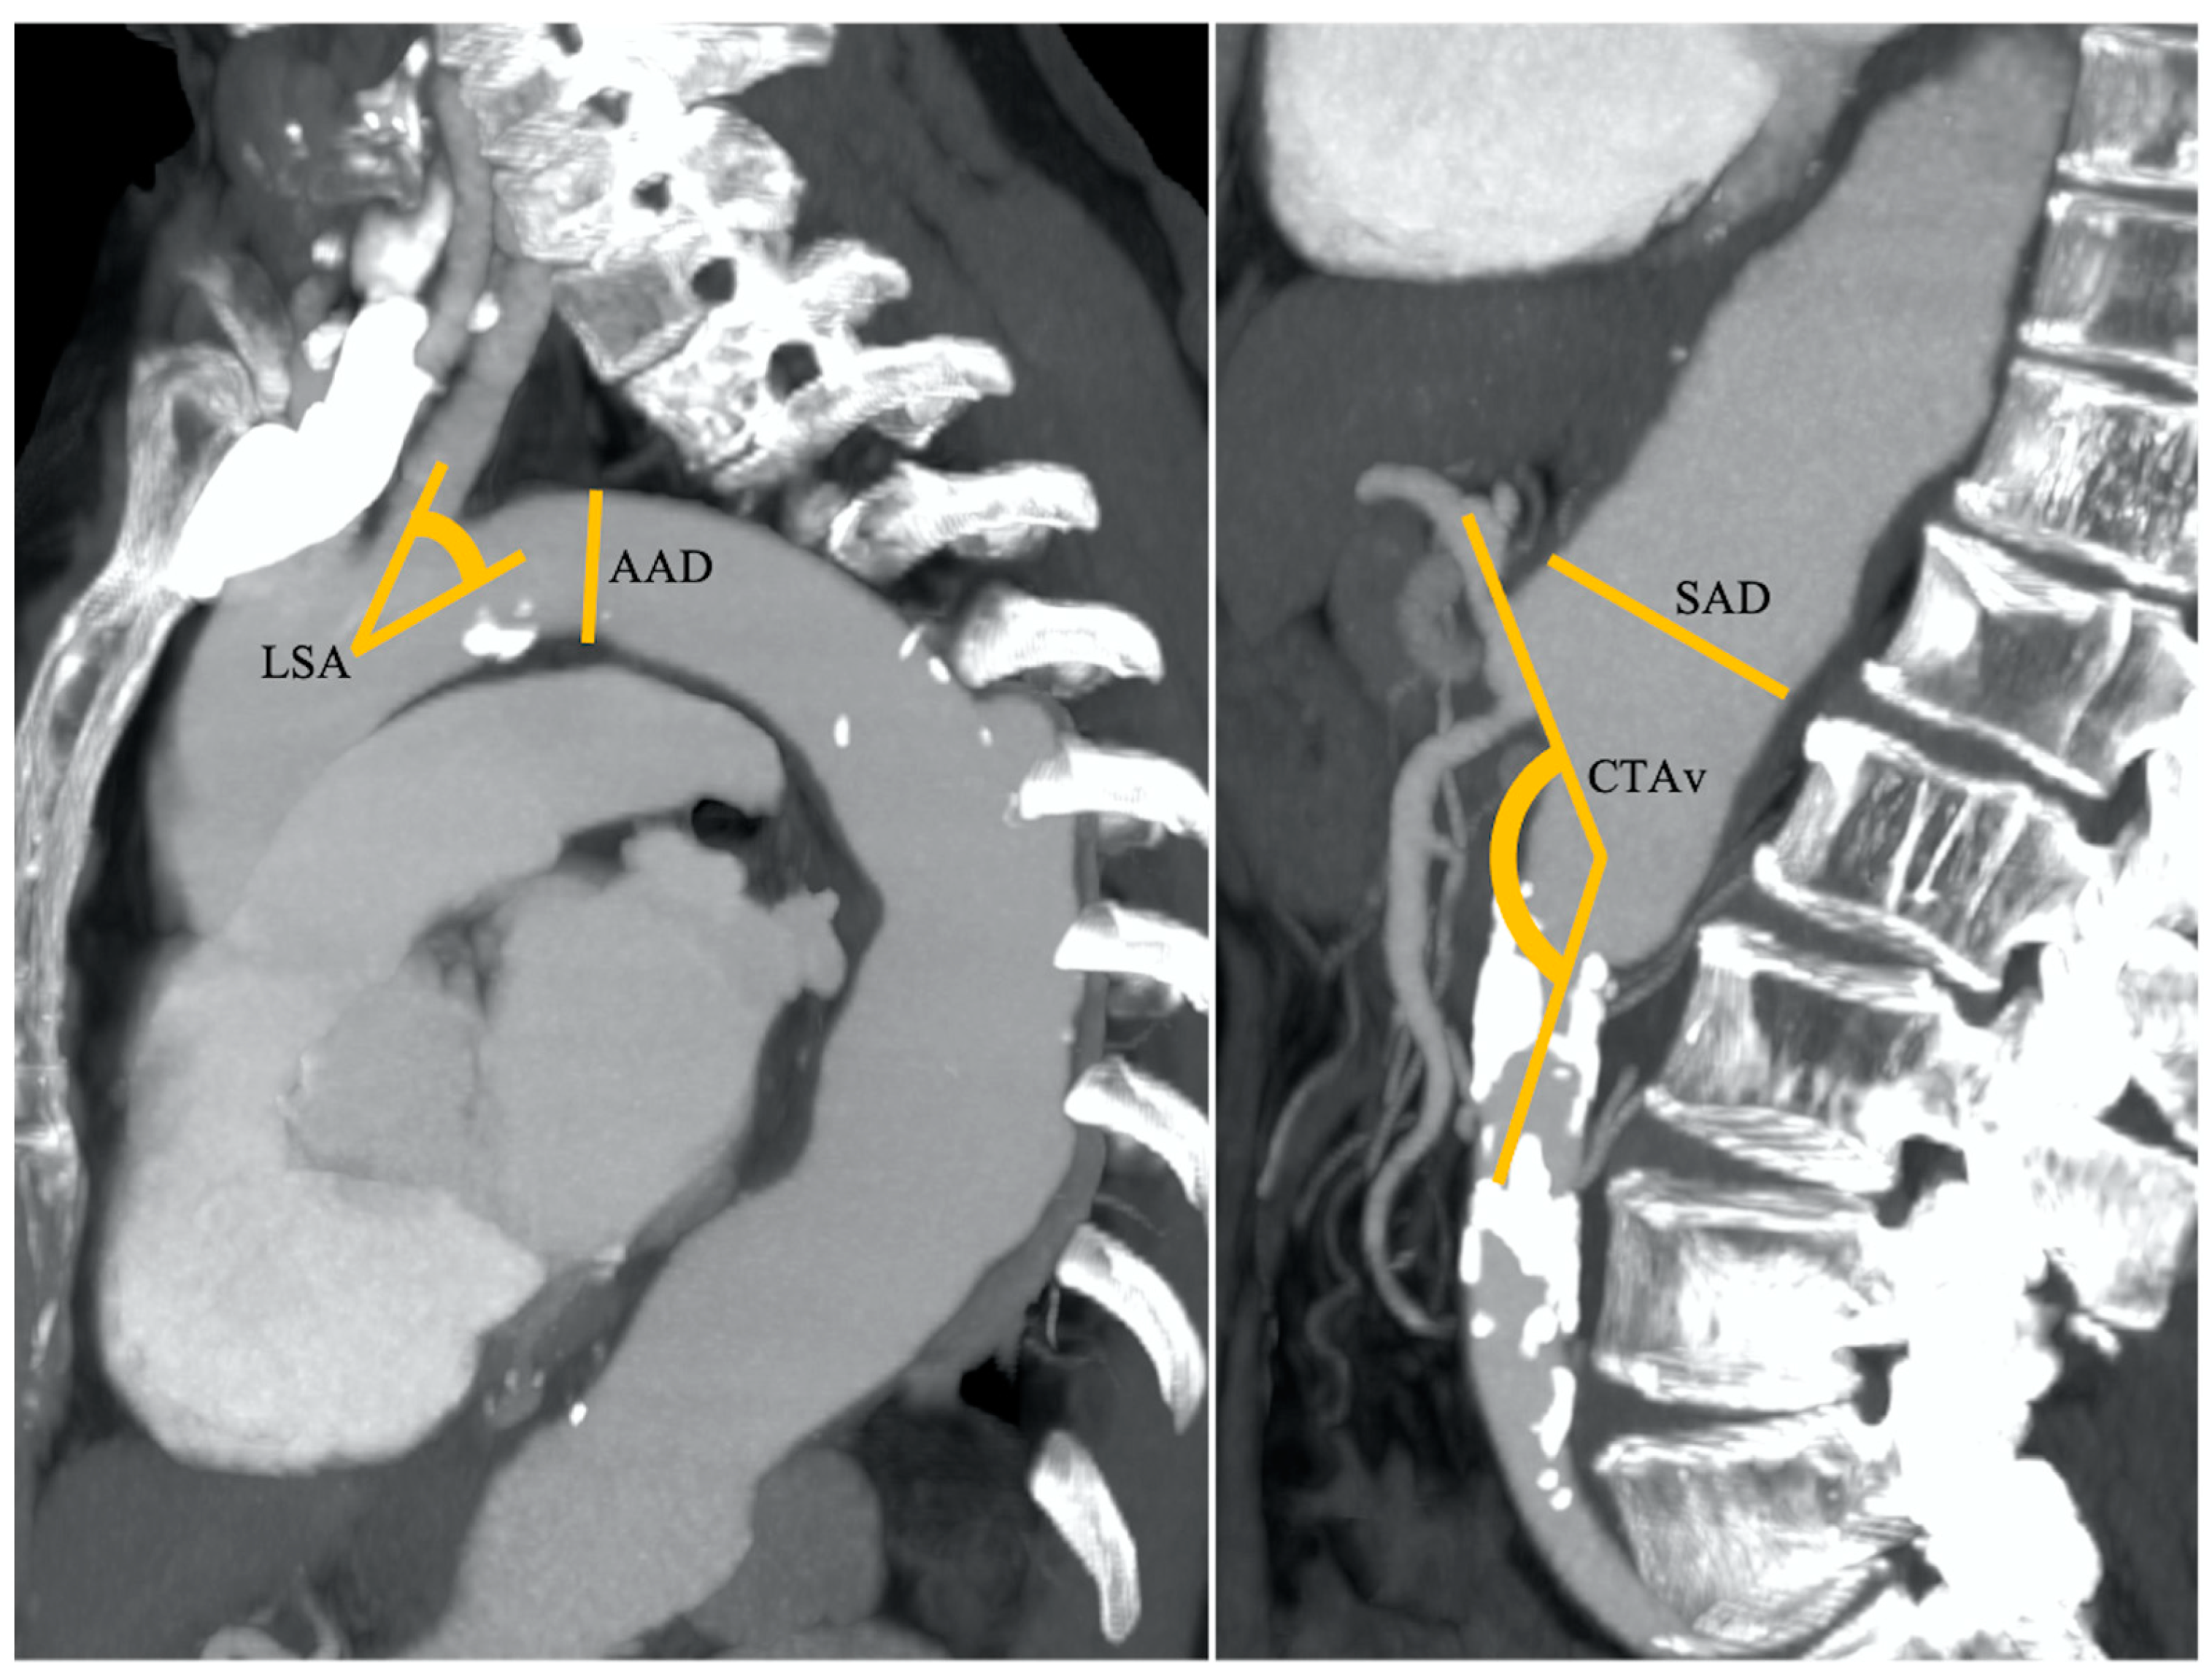

Figure 1. A 52-year-old patient with nodular HCC in the left liver lobe with a radial diameter (RD) of 3 mm (0 points), left subclavian artery angle (LSA) of 85° (0 points), an aortic arch angulation (AAA) type I (0 points) with a diameter (AAD) of 32 mm (1 point), suprarenal aorta diameter (SAD) of 23 mm (0 points), and celiac trunk angle (CTA) of 45° (0 points). Final RAD-access score: 0, transradial access preferred for values between 0 and 2.